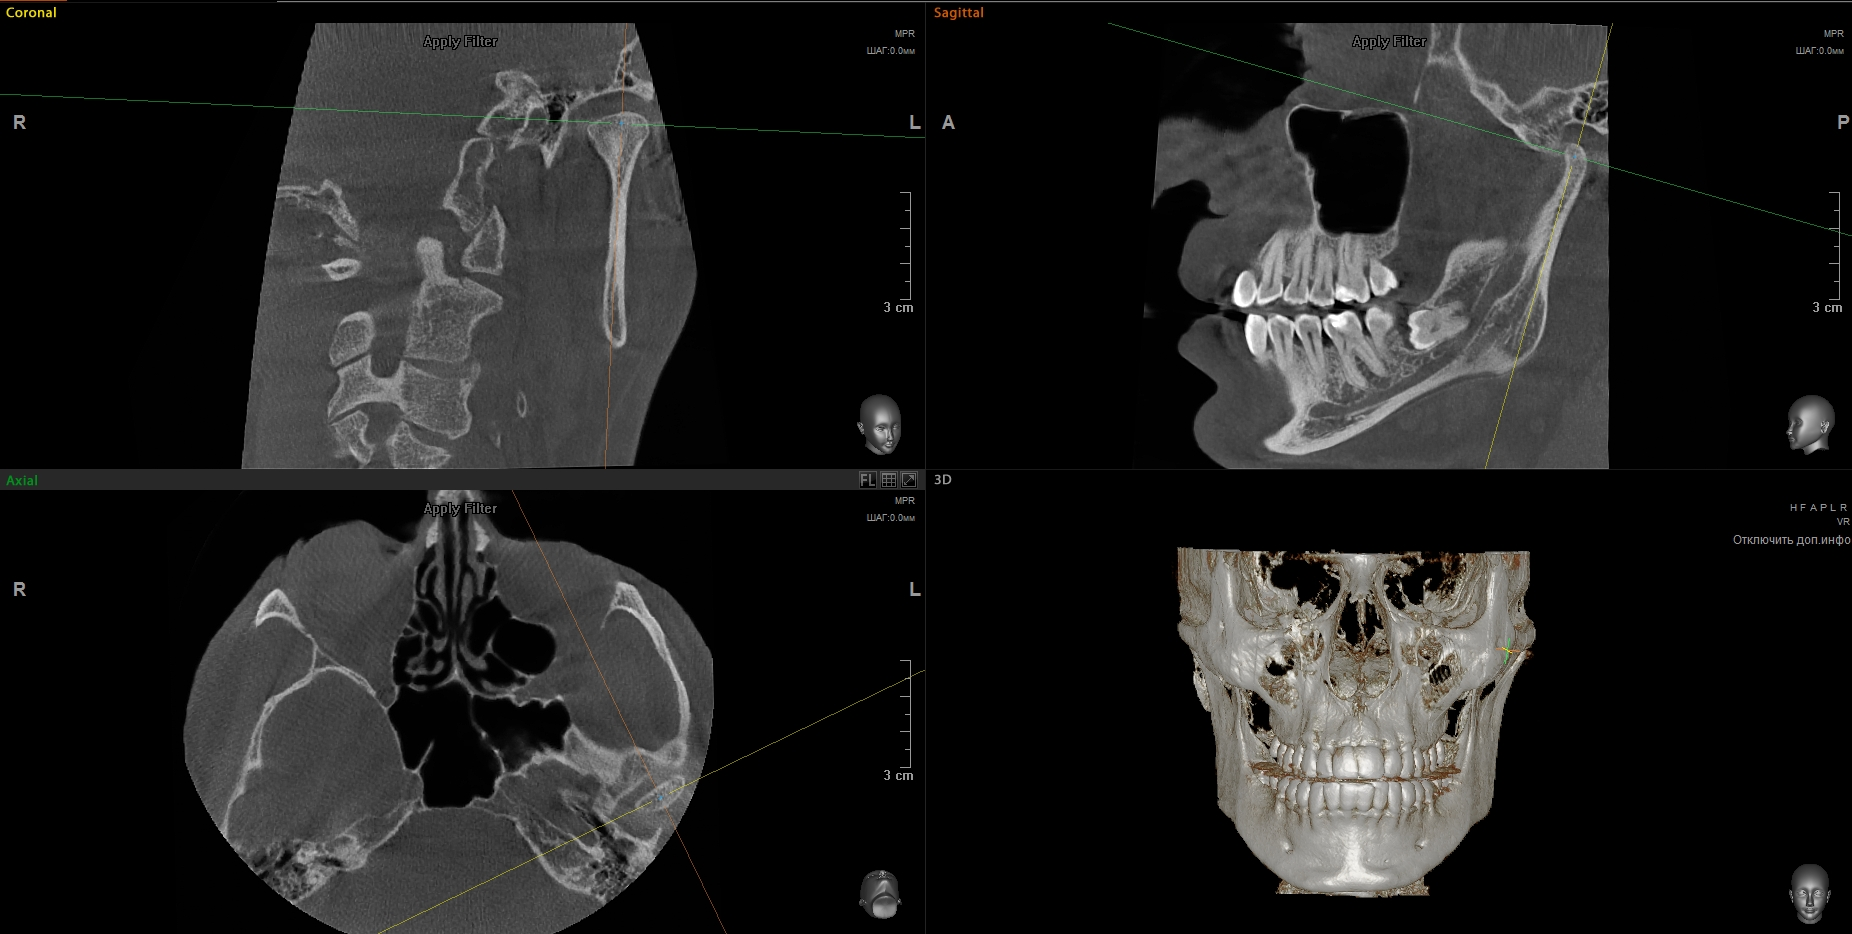

Computed tomography of the jaws

Detailed imaging of the jaws and the mandibular joint